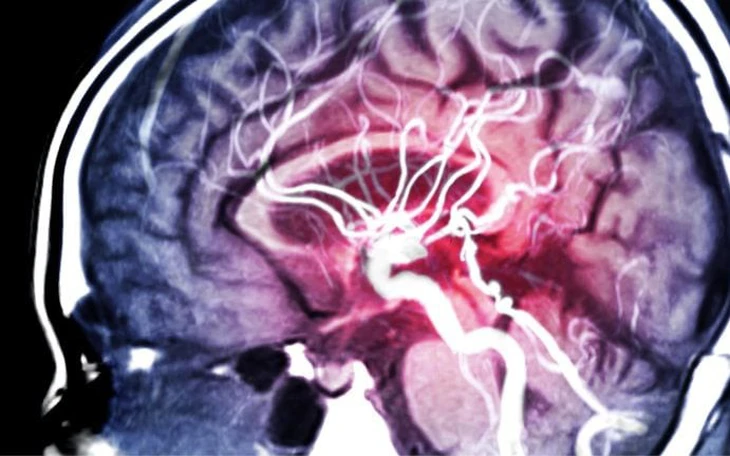

Thói quen ăn uống ảnh hưởng đến sức khỏe não bộ - Ảnh: FREEPIK

Thói quen ăn uống ảnh hưởng đến sức khỏe não bộ